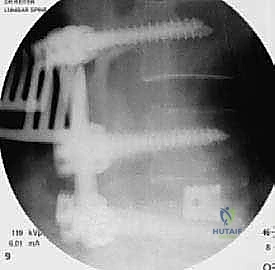

| عدد الأقفاص (Cages) | يتم وضع قفصين (واحد في كل جانب). | يتم وضع قفص واحد كبير مائل. |

يتم وضع المريض على بطنه. يتم عمل شق جراحي دقيق في أسفل الظهر. باستخدام أجهزة الملاحة الجراحية والأشعة السينية الحية (Fluoroscopy)، يتم تحديد المستويات الفقرية المستهدفة بدقة.

الخطوة 4: زراعة القفص والطعم العظمي (Cage Insertion)

يتم إدخال قفص مصنوع من مادة PEEK أو التيتانيوم، مملوء بطعم عظمي (يؤخذ غالباً من المريض نفسه أو طعم صناعي)، في المساحة الفارغة. هذا القفص يعيد الارتفاع الطبيعي للفقرات ويخفف الضغط عن منافذ الأعصاب.